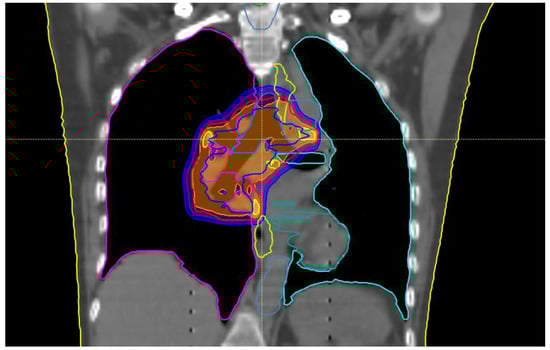

2. Case Presentation